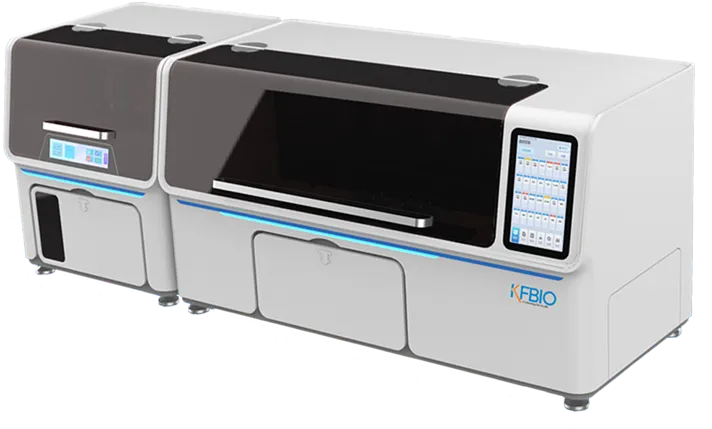

KF-FL-400

Digital Pathology 400

Slides Scanner fluorescence

High-throughput, Fast, Stable,

Continuous scanning

Scientific research, clinic,

FISH analysis, molecular typing